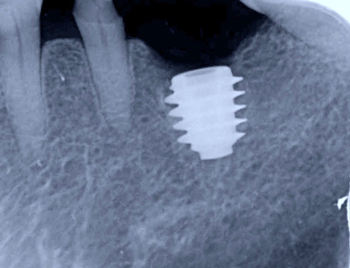

ノーベルバイオケア社製のアクティブ直径5㎜、長さ11.5㎜を移植完了。

インプラント移植直後の状態。周囲の骨は抜歯の影響で、スカスカ空洞があります。

吸収性の人工骨に患者様御自身の血液で製作したコラーゲンとフィブリンの塊を混ぜて、不足している

骨の部分に添加しました。

コラーゲンの塊をシート状に圧縮して確実な骨の再生を促します。